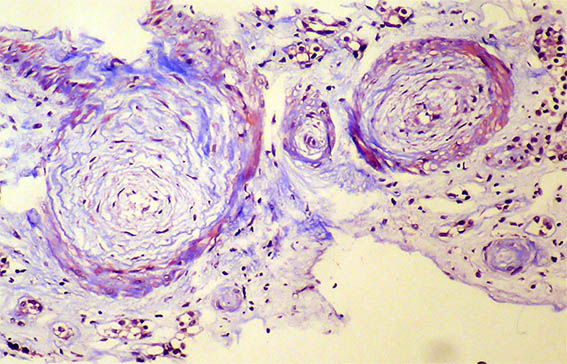

Figure 1. Masson's trichrome stain, X100.

Figure 2. Masson's trichrome stain, X200.

Figure 9. Masson's trichrome stain, X200.